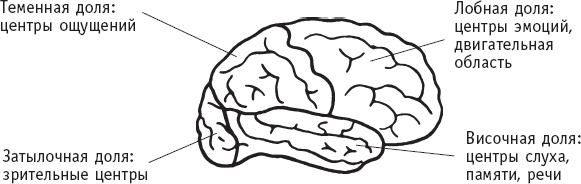

Головной мозг разделен на правую и левую половины, или полушария. Внешняя область мозга – это бугорчатая серая масса нейронов, называемая корой мозга и ответственная за такие сложные функции, как память, сознание, интеллект, мыслительные процессы и сенсорное восприятие. Каждое полушарие разделяется на четыре основные доли, каждая из которых отвечает за конкретные функции.

Доли полушарий головного мозга и их функции